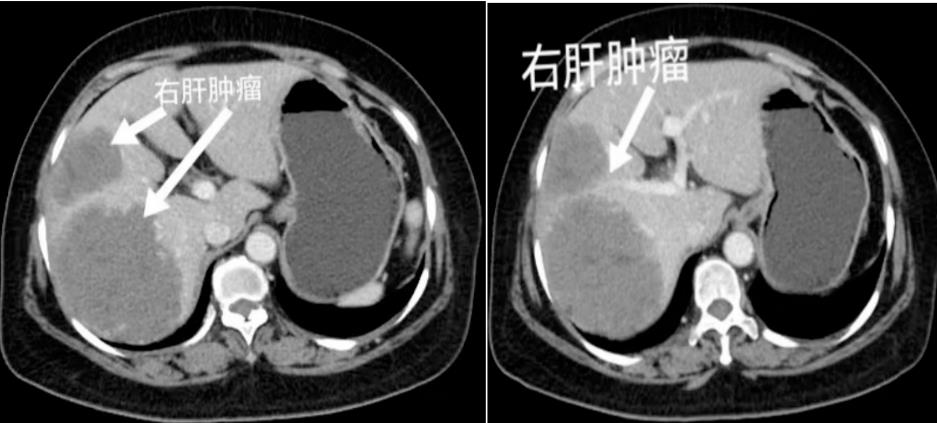

近日,红河州第三人民医院(红河州肿瘤医院)收治外地一位老年女性患者,因“上腹部疼痛3周”到当地医院就诊,行腹部CT检查发现肝右叶多发占位,建议到上级医院进一步就诊。随后,患者到红河州第三人民医院就诊,门诊以“肝占位”收住肝胆外科治疗,完善相关检查后,诊断右肝巨大肿瘤。

在徐耀端科主任的主持下,经过全科讨论,为患者制定了“荧光导航4K腹腔镜解剖性右半肝切除术”的治疗方案,并于2023年3月23日为该患者成功实施手术。